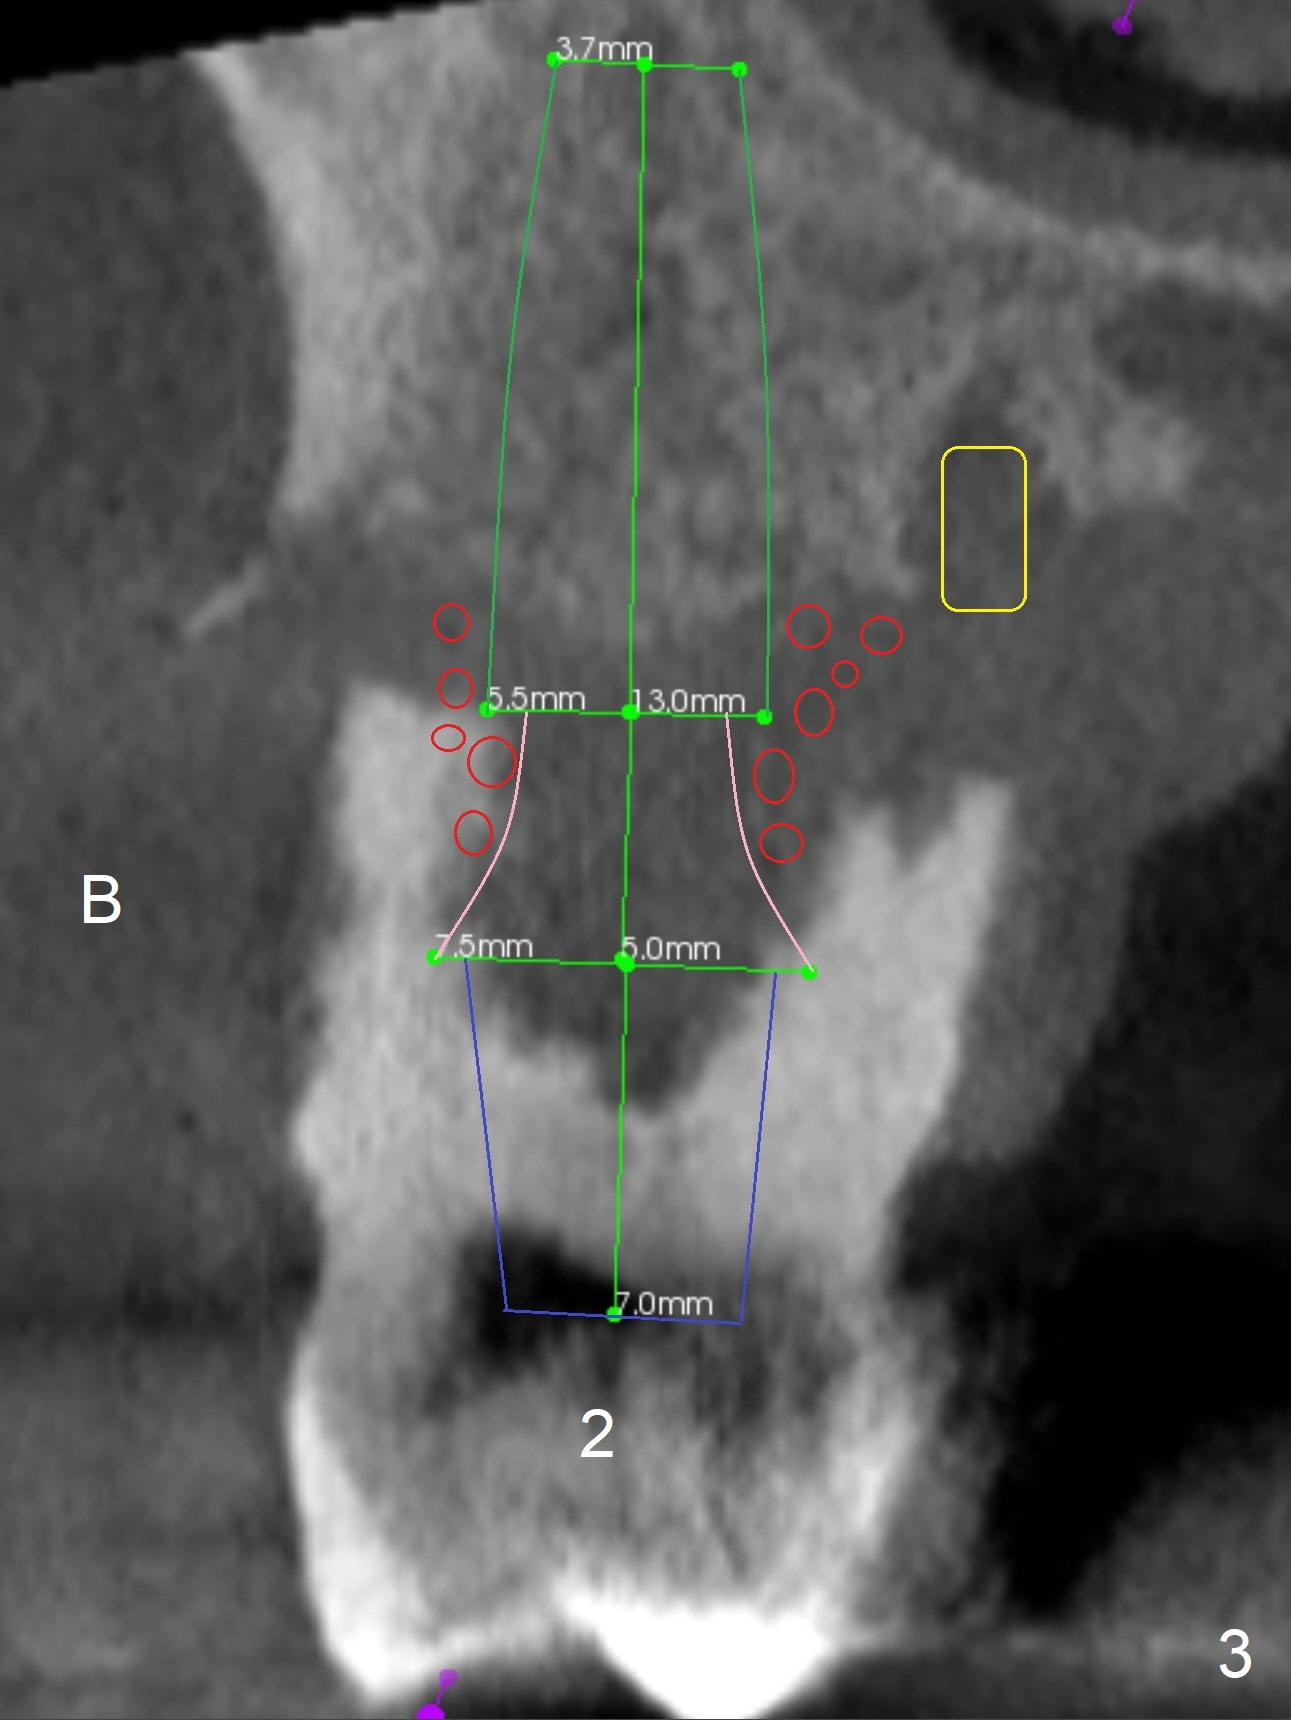

Extract #2 or remove #3-5 FPD first whichever is looser. Use the other as reference guide. Place Osteogen plug in the palatal socket of #2 ad 3 (Fig.3,4 yellow box) and allograft around the implants (red circles).